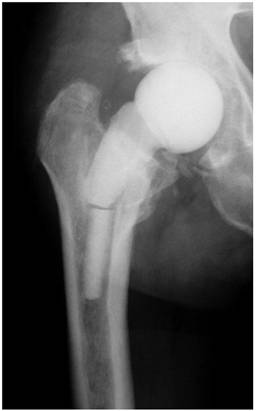

In cases with muscular insufficiency or large acetabular defects, the spacer should not be implanted as a hemiarthroplasty, but rather as a total arthroplasty, consisting of a spacer stem and a cup (Figure 3). This is also of benefit in cases where the spacer head is too small for the acetabulum cavity. Since not every department has molds for production of spacers in different sizes or lengths or the costs for commercially available hip spacers are extremely high, the orthopaedic surgeon is commonly faced with the dilemma: should a larger, hand-molded spacer head be implanted (which, however, has the disadvantage of an inferior articulation due to the uneven head surface and form) or, alternatively, a spacer cup is inserted into the acetabulum. We recommend the second option. This implantation technique also offers the advantage of a prevention of a spacer migration into the pelvis (Figure 4) beside a normal articulation and prevention of any spacer dislocation. Hereby, the cement-cement articulation promotes the emergence of high local antibiotic concentrations due to the continuous friction of the articulating components. Cement debris can be then easily removed at the time of the prosthesis reimplantation via pulsatile lavage and debridement. However, in some cases with a combined muscular insufficiency and large acetabular defects a spacer dislocation might still occur. These cases should be also considered as candidates for a resection arthroplasty.

Figure 3

Articulating hip spacer consisting of a spacer cup and -stem.